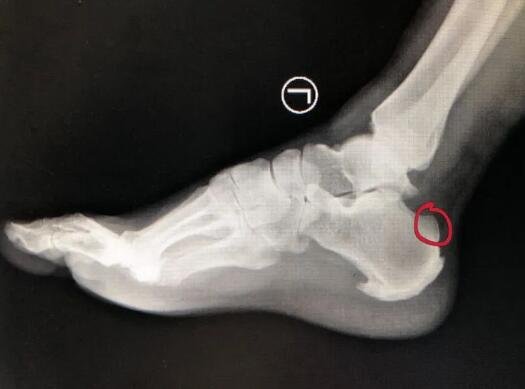

于是来到betway在线登陆足踝外科求诊,接诊的医生检查发现其左跟腱止点处压痛,提踵试验阳性。结合病史体征、辅助检查符合跟腱止点炎诊断。

为更好的保护患者关节,减少创伤,手术团队准备通过踝关节镜行“踝关节镜下清理骨赘切除跟腱止点重建术”。

术中,医生通过踝关节镜下观察病变部位,清理骨赘,切除引起疼痛的跟腱止点,刨刀结合等离子清除增生炎性滑膜。踝关节镜下小骨刀、游离体抓钳清理增生骨赘,并重建跟腱止点,缝合跟腱组织。术中,仅仅2个不足1mm的伤口,在镜下重建跟腱止点,减少创伤。